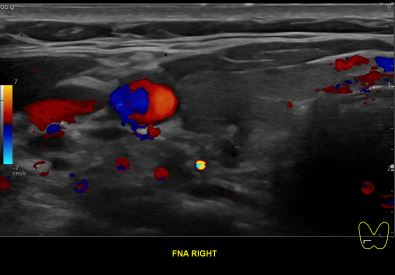

상기환자 외부건진이상소견 추적관찰위해 내원하신 50대중반 여성분으로

의심스러운 갑상선 우엽 세포검사 진행후 갑상선암으로 진단되었습니다